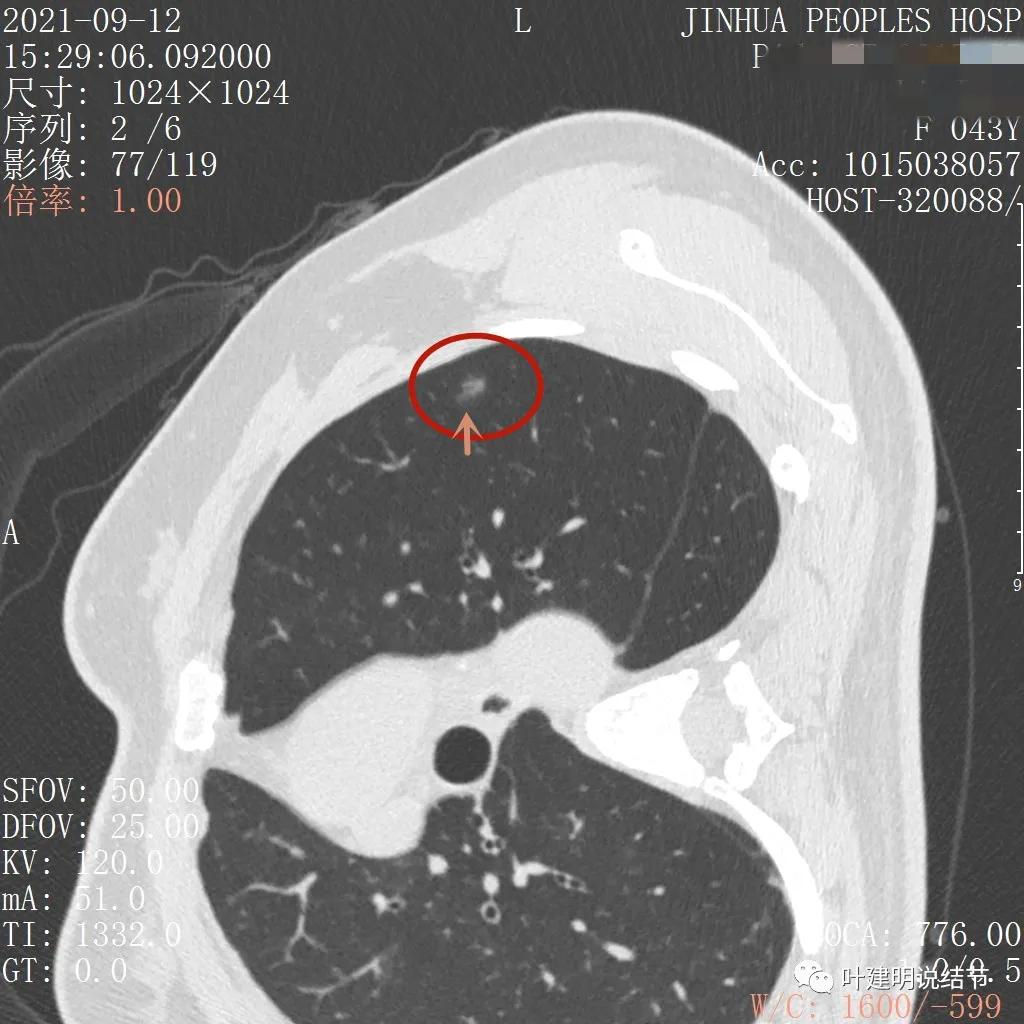

金华的某A,女性,今年43岁,检查发现左肺上叶结节2月余。其于当时说是在外院检查发现,到我门诊找我看过的(我是记不清楚了),大概是告诉她:考虑早期肺癌可能性大,但密度还低,边缘显模糊。让她再随访观察下再决定手术与否。这次送孩子上大学后,她马上来医院全面检查并若需要手术就决定手术了的。我们先来看她的平扫片子:

可见左肺上叶磨玻璃结节,边缘略显模糊,瘤肺边界不是很清,但总体上看,病灶轮廓仍是较为清楚的,而且有所层面有微小血管进入,病灶密度也不均匀,感觉有点杂乱。这种病灶如果随访了2个多月仍持续存在,也没多少变化的话,基本上要考虑肿瘤范畴的结节。为了看细节,我们建议其再查了靶扫描,图像如下: